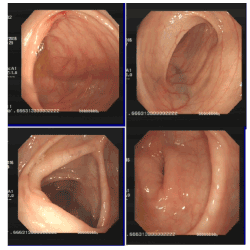

Figure 1. Esophagitis (fungus)Multiple apophysis lesions mul (polyus?), Duodenal bulb inflammation